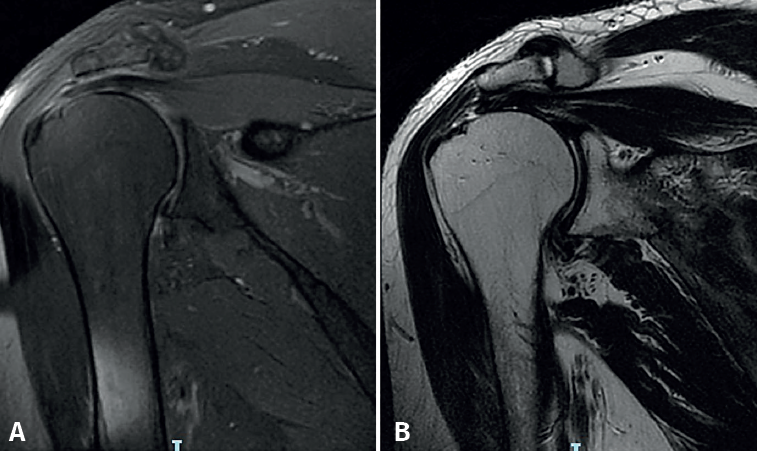

Reduction phase in the second row (Figure 2A)

In the reduction phase in the second row, the tendon is reduced to its footprint by knotting the Loop Lasso®traction stitches at its free margin with the sutures of the anchors of the second or central row. The two strands of each suture are retrieved together in the subacromial space through the PSL portal for the posterior anchor and the ASL portal for the anterior anchor. Knotting is started at the most posterior suture while maintaining traction reduction of the anterior sutures. The type of knot used is the so-called easy knot, followed by half stitches to complete a "surgeon's knot" configuration. The same procedure is carried out successively on the other three sutures, and the remaining strands are cut.

Compression phase in the second row (Figure 2B)

In this phase, the four sutures (8 strands) corresponding to the anchors of the first or medial row are knotted. For this purpose, the sutures of the posterior anchor will have been retrieved through the PSL portal and those of the anterior anchor through the ASL portal. The type of knot used at this stage is the slip knot (in our practice, the giant type), followed by three half safety knots. Only one of every two remaining strands is cut. In this way, an adaptation of the end of the tendon to the entire footprint will have been achieved.

Tightening phase in the third row (Figure 2C)

In this last phase involving tightening in the third row, the remaining four strands that have not been cut from the knots of the first row are recovered in criss-cross fashion. Each two of them are threaded into respective so-called "second-row" anchors without sutures. They are then slipped into the subacromial space with the aid of a metal hemi-cannula, and are inserted up to the mark in the previously made orifice. The sutures are tightened and clamped by threading the plunger on the anchors. The entire anchor is impacted, the insertion rod is removed, and the strands are cut. In this third row, we use FootPrint Ultra PK®(Smith & Nephew Inc., Andover, MA, USA) or Quattro® Link (Zimmer-Biomet, Zug) anchors. Finally, the result is assessed and the portals are sutured.